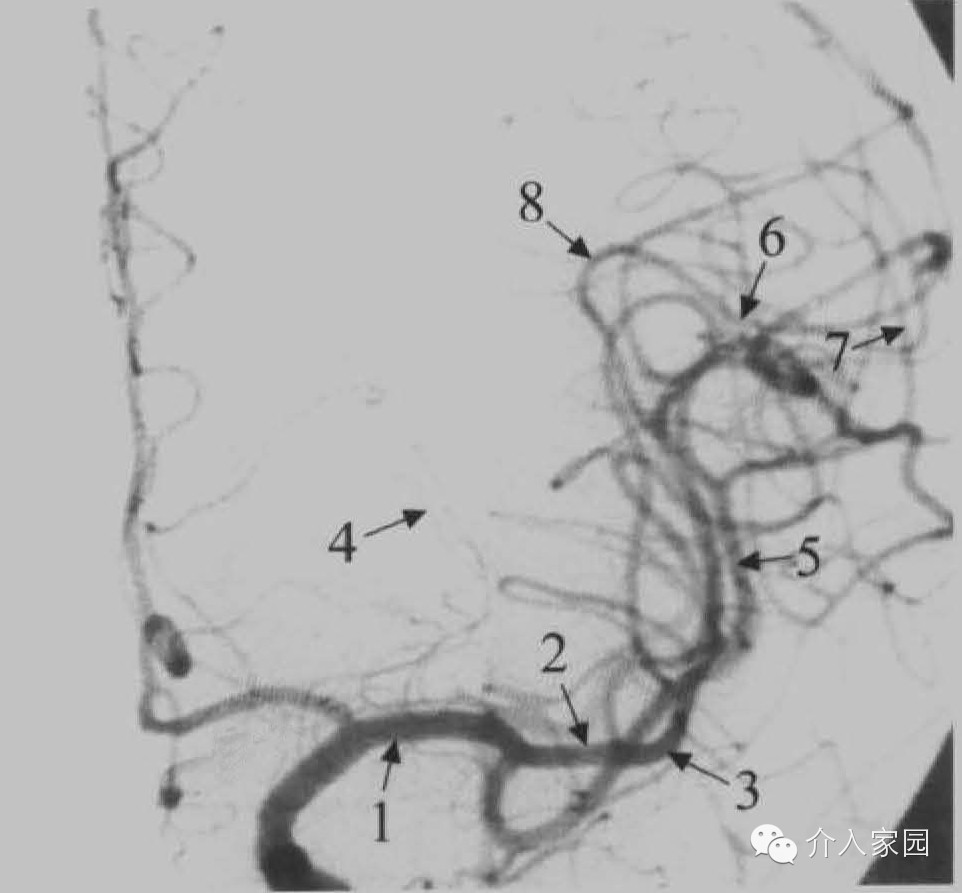

再來一張DSA造影正位圖:

解說:

1=Ml段(分叉前段)

2=Ml段(分叉後段)

3=大腦中動脈膝部,也就是M1及M2分界處

4=豆紋動脈

5=M2段

6=M3段

7=M4段

8=側裂頂端(血管造影側裂點),也是M2與M3分界處。